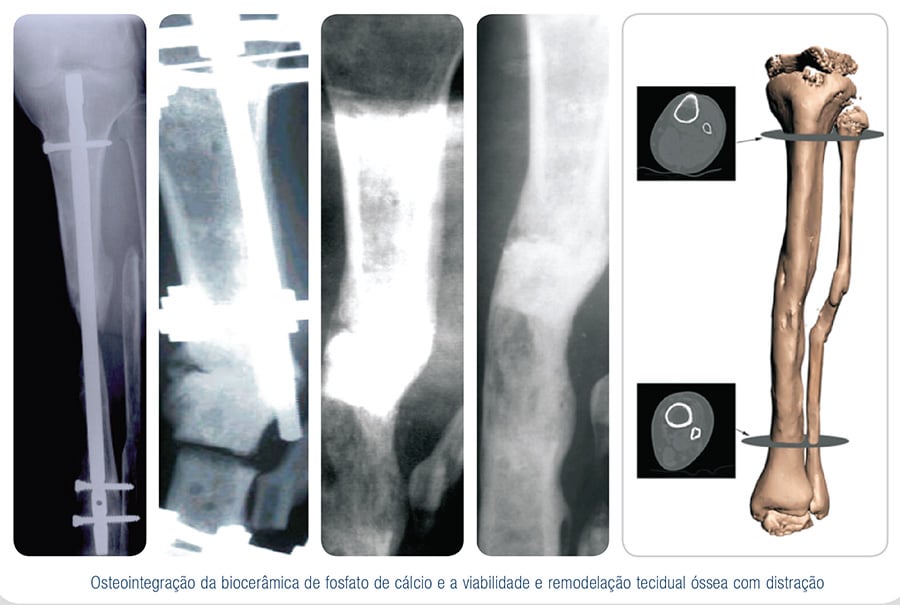

As biossoluções EincoBio para uso na Traumato-Ortopedia criaram novas alternativas com vantagens significativas, principalmente quando substituem materiais de origem orgânica, com a correta indicação naqueles procedimentos.

Com as mais variadas apresentações destes materiais fosfocálcicos, a reconstrução óssea e manutenção de espaços anatômicos, hoje tornam-se uma rotina com a aplicação dessas biossoluções.